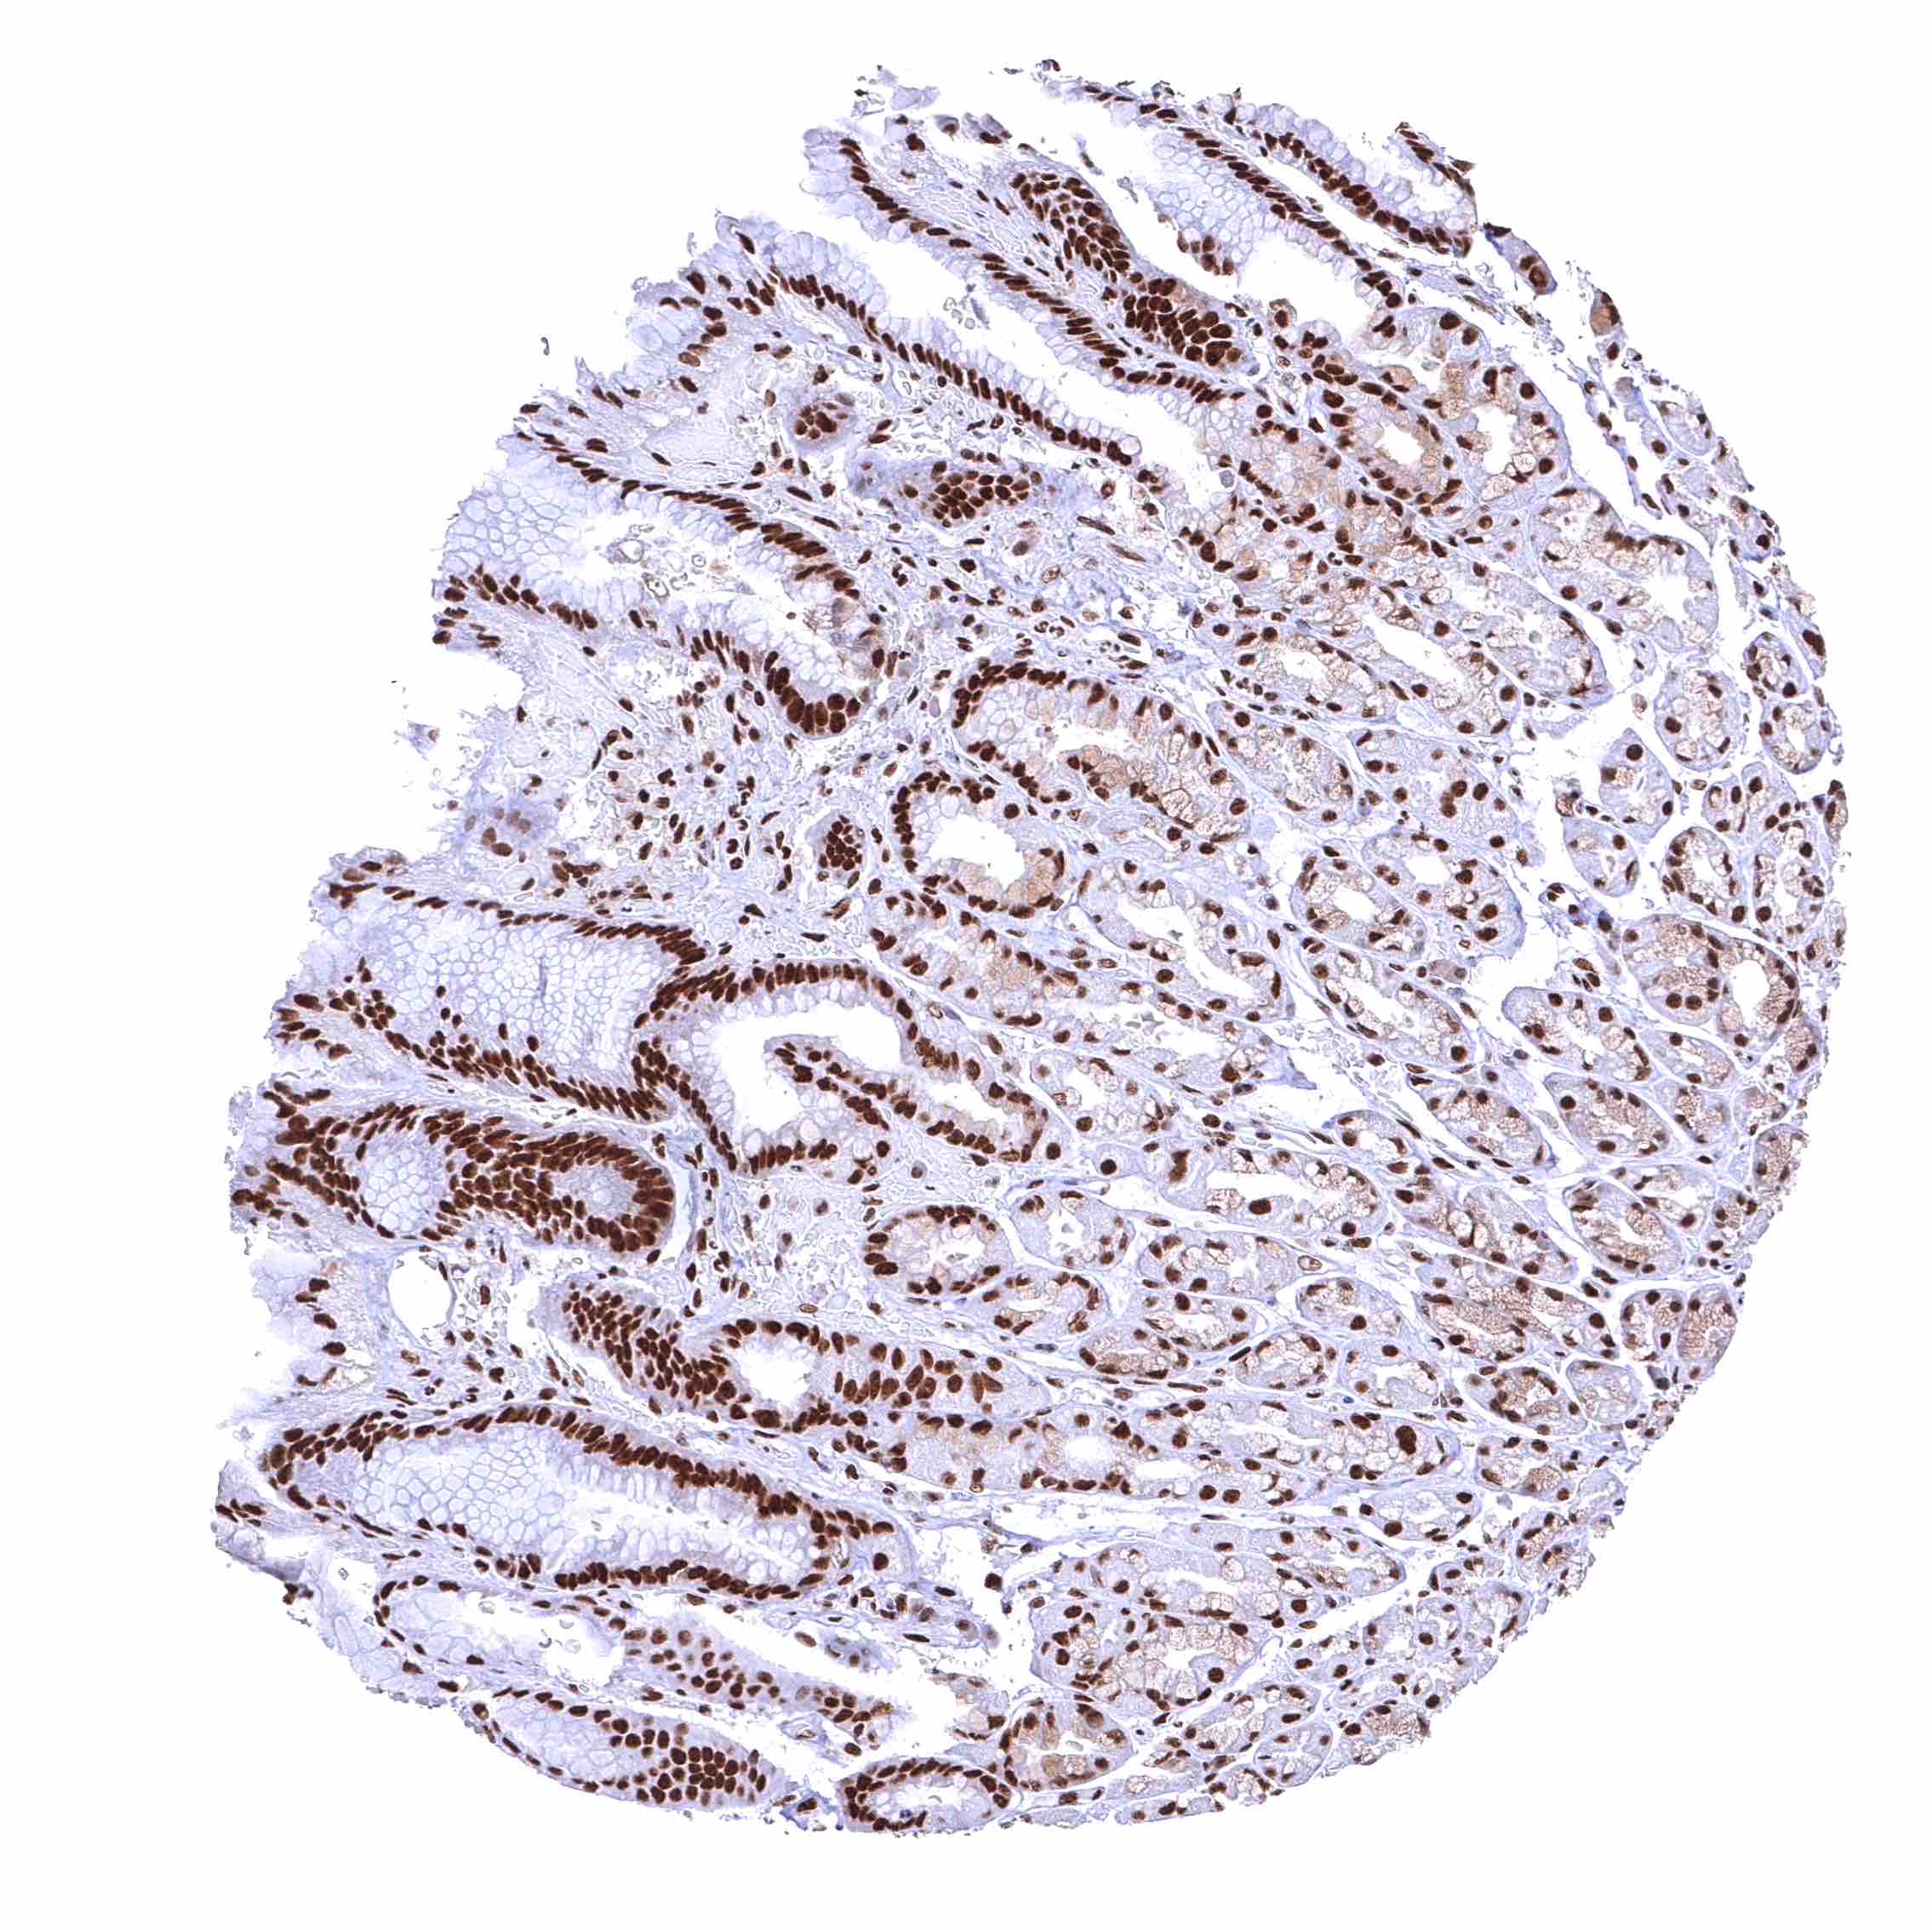

Colon descendens, mucosa – Nuclear BRD4 staining of surface epithelial cells is weaker than in crypts.